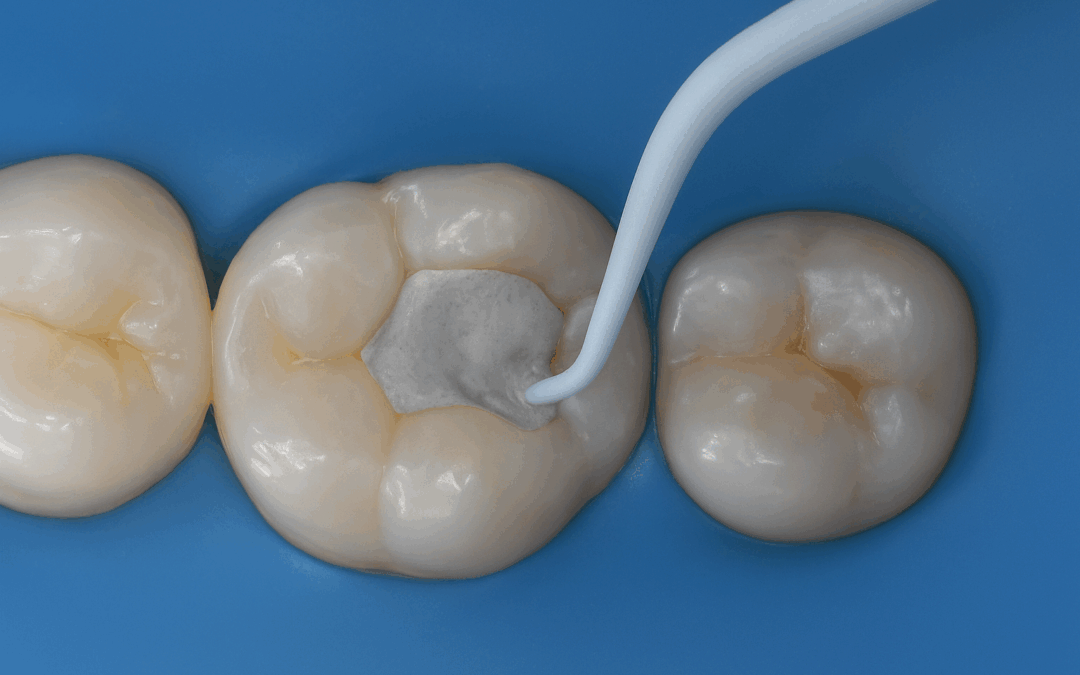

Biodentine™ XP – bioaktywny cement, który ratuje zęby Biodentine™ XP to nowoczesny, bioaktywny cement stomatologiczny, który nie tylko uzupełnia ubytek w zębie, ale też wspomaga jego naturalną regenerację. Stosowany jest przez stomatologów m.in. w leczeniu głębokiej...